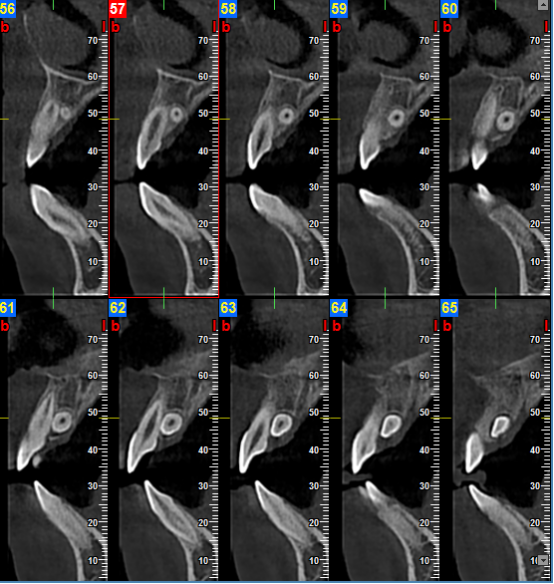

颞下颌关节检查单次扫描即可通过矢状和冠状图像观测到关节间隙的改变和是否发生病理变化。3D影像重建可以清晰提供颞下颌关节、关节头及关节颈部详细解剖信息。